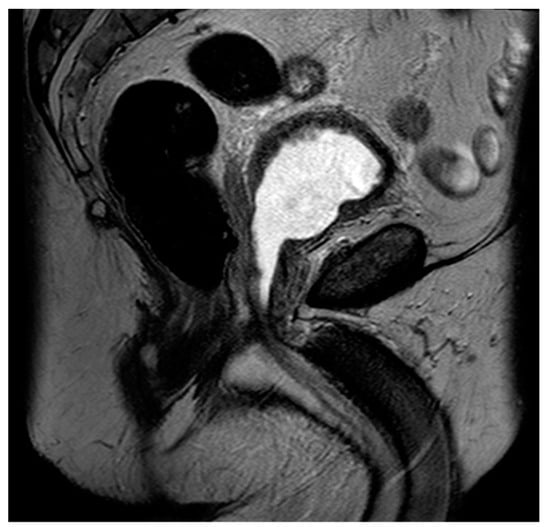

Figure 8. Sagittal T2 image of the pelvis demonstrating a complete absence of the prostate gland with vesicourethral anastomosis following RP.

Radical prostatectomy (RP) is a definitive treatment option for men with prostate cancer in which the prostate and seminal vesicles are surgically removed. The surgical removal of the pelvic lymph nodes may also be offered to men when the chance of nodal metastasis is 2% or higher [81]. Multiple surgical techniques have been described for RP, but the most common approach is robotic-assisted laparoscopic radical prostatectomy (RALP), with up to 90% of all prostatectomies being performed in this manner [82]. Regarding MRI, post-RP changes demonstrate the absence of the prostate gland, with a vesicourethral anastomosis that should have a low T2 signal without early enhancement, nodularity, or restricted diffusion (Figure 8).